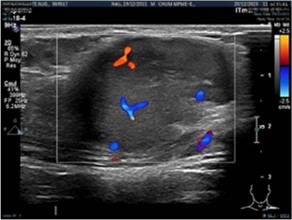

Ultrason showed a well-limited tissue mass of (39 × 23 × 21 mm) within the vascularized trapezius muscle on doppler (Figures 2).

Figure 2: Ultrason findings.